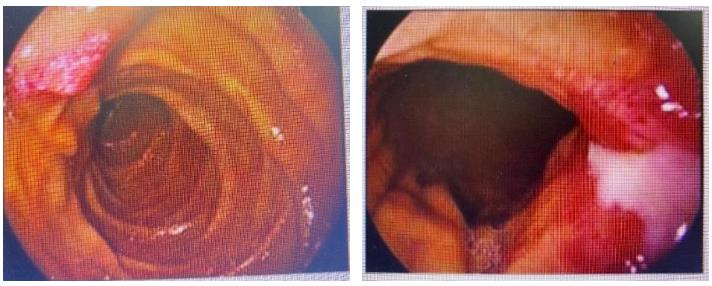

胃镜:贲门下方、胃体前壁、胃体小弯侧、胃体后壁见巨大溃疡性肿物,考虑胃癌并出血。

图2.胃镜

2022-03-01胃镜:贲门下方、胃体前壁、胃体小弯侧、胃体后壁黏膜粗糙不平,胃体后壁溃疡对比既往胃镜检查明显缩小。

图5.治疗5周期后胃镜